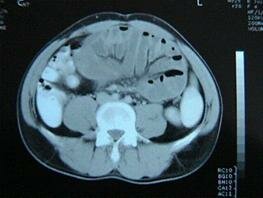

Abdominal Cocoon: A Rare Cause of Intestinal Obstruction

E Altinli, MD, A Sumer, MD, AD Celik, MD